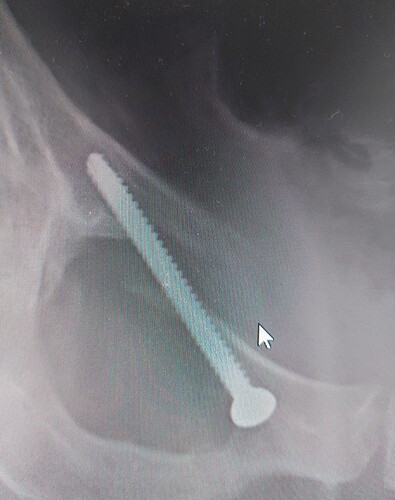

Hier, der Part übrigens, bei dem die Knochen sich nicht mal ansatzweise zu treffen scheinen

Aber ist wohl kein Problem. Das KH sagt, sieht gut aus. Ich darf jetzt sitzen. Whoop whoop. Boah, was ich jetzt am liebsten alles machen würde, haha

Ich glaube die haben ne Schraube in deinem Körper vergessen

Nicht nur eine

Kommen erst in nem Jahr raus

Hast du keine Schrauben aus Magnesium bekommen, die vom Körper irgendwann abgebaut werden?

Wanesser got totally screwed

In einem Jahr holen sie dann die Nickelback.